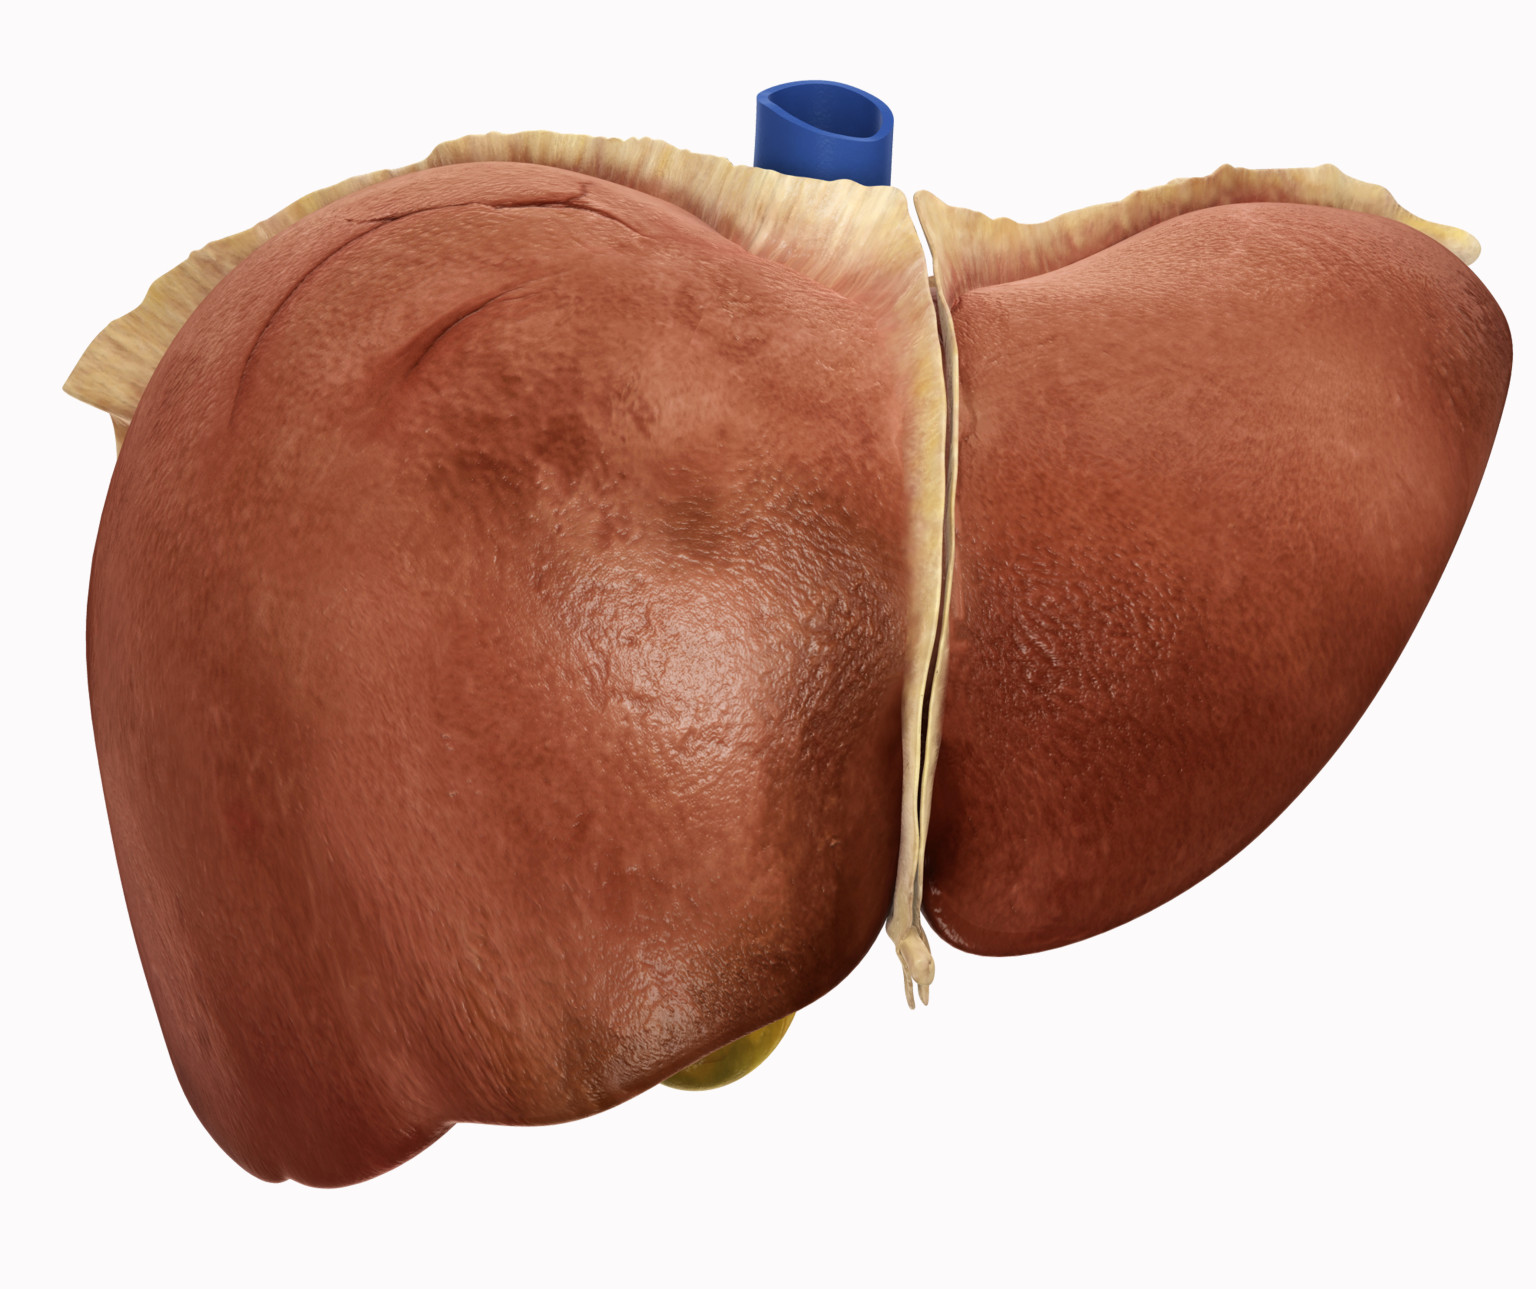

Comparison of a Healthy Liver and one Damaged by Cirrhosis – ZBrushCentral

Comparison of a Healthy Liver and one Damaged by Cirrhosis – ZBrushCentral